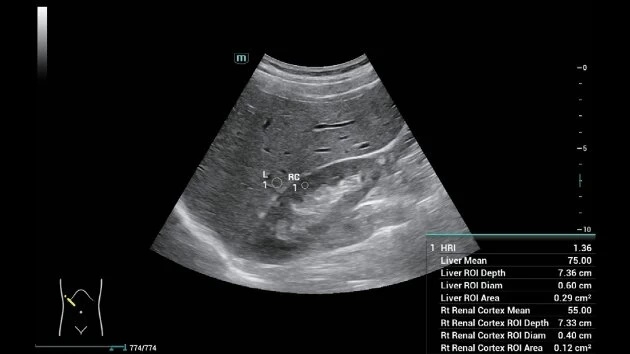

• Звуковая сенсорная эластография (STE) для точной оценки жесткости тканей

• HR Flow™ — поток высокого разрешения